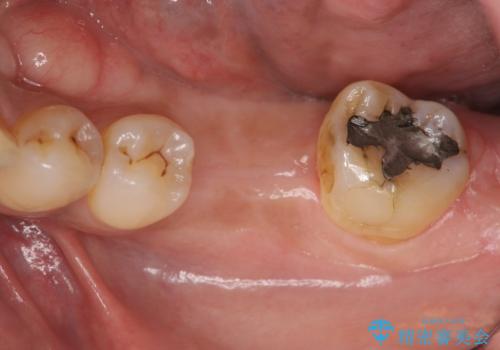

失った奥歯をインプラントで機能回復

- 失った歯の機能回復を希望され来院されました。

取り外しの必要な入れ歯、隣の歯を削る必要のあるブリッジに心理的抵抗があり、インプラントを用いて咬合機能を回復していくこととなりました。

元あった歯のようにしっかりと咬合機能が回復することができました。